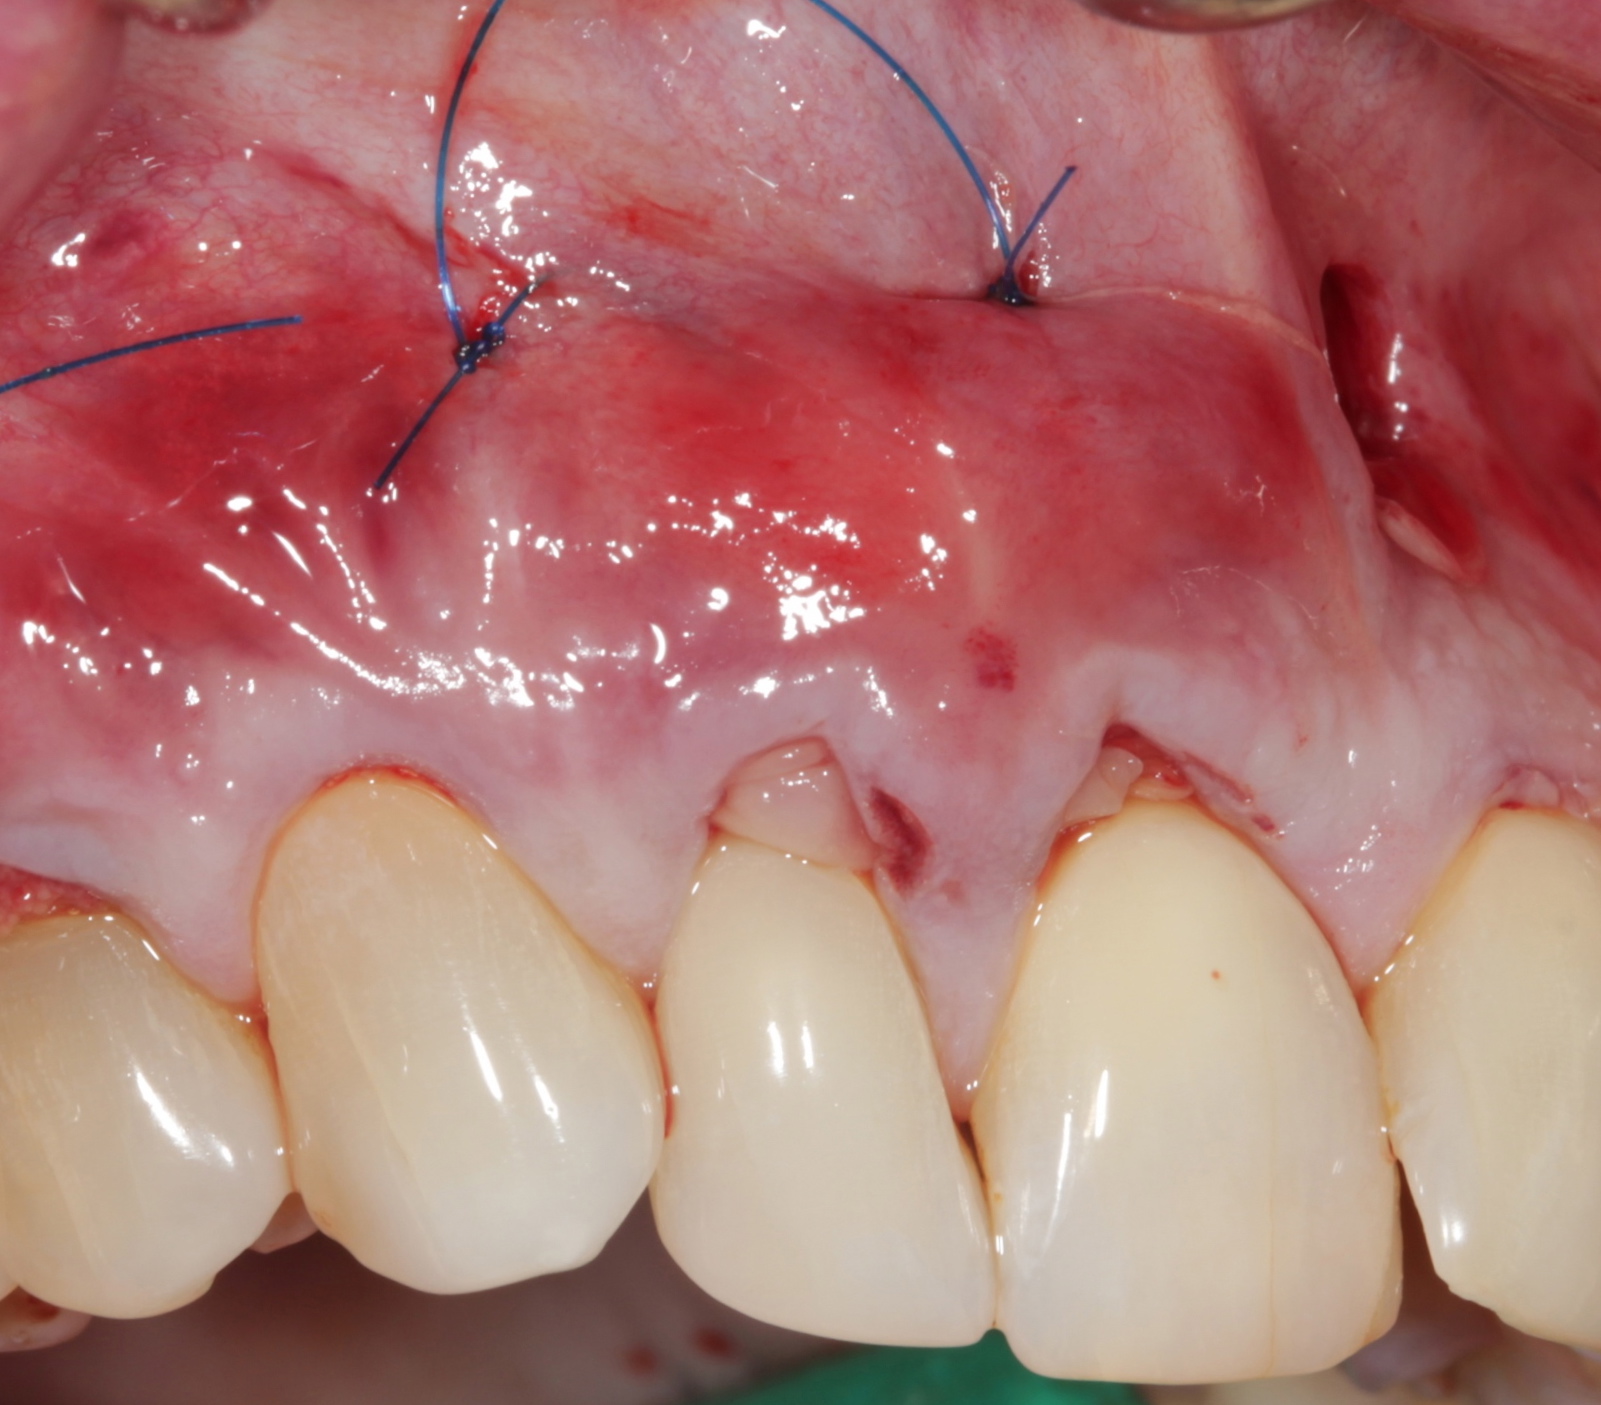

Fig 8. Apical periosteal suture below the mucogingival junction will “lift” the APRF/flap complex coronally. This intimate proximity of the APRF membranes with the periodontal ligaments will allow for a slow release of growth factors, thus promote keratinization.

Figure 8